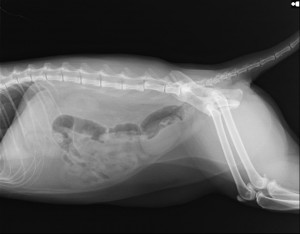

術後レントゲン

コメント;

術前に存在した腰椎間のずれは整復され、4本のφ0.7mmの田島式Kワイヤーとアリゲータープレートにて固定されています。